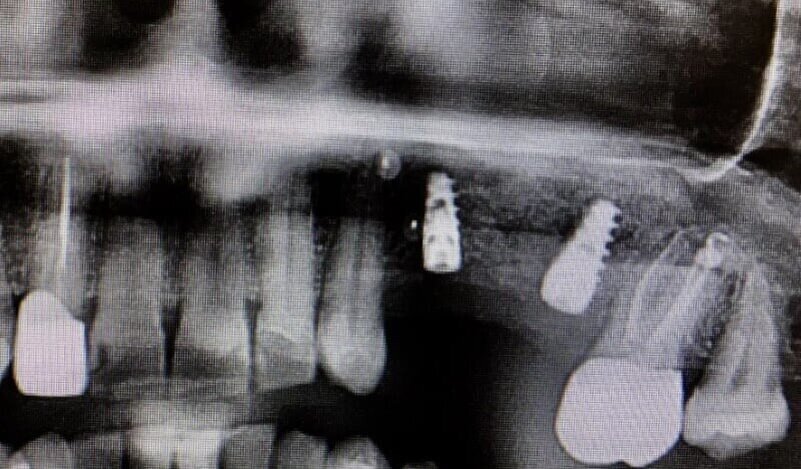

In questo case report è stata selezionata una paziente di sesso femminile, S.P. (54), non fumatrice, con buona igiene orale e con anamnesi negativa all’assunzione di farmaci, ad allergie, disturbi metabolici e patologie sistemiche (Figg. 1-3). È stata proposta una tecnica di rialzo del seno mascellare eseguita mediante strumenti piezoelettrici (Piezosurgery®, Mectron, Genova, Italy) (Figg. 9, 10, 13).

Per la fase post-operatoria sono stati prescritti un analgesico da prendere al bisogno (Paracetamolo 500 mg), cortisone (Bentelan 1 mg, 4 compresse il primo giorno e a scalare i giorni successivi fino ad 1 il quarto giorno) e clorexidina 0.2% e sono state fornite istruzioni complete all’igiene orale. Dopo 7 giorni dall’intervento è stato prescritto nuovamente aerosol (beclometasone dipropionato Clenil 0,8 mg/2 ml) e soluzione ipertonica (Libenar 22g/l per 7 giorni). La sutura è stata rimossa dopo 10 giorni. A distanza di 7 mesi dalla procedura rigenerativa è stato attuato un secondo timing chirurgico per posizionare gli impianti nella sede prestabilita. Eseguita l’anestesia locale sono stati inseriti impianti endossei in posizione 24 (3.2 x 10 mm.) e 26 (4.3 x 10 mm) (JD Evolution Plus - JD Dentalcare, Modena, Italy) (Figg. 17, 18) ed eseguita la radiografia di controllo postoperatoria. La rimozione delle suture è avvenuta dopo 10 giorni.